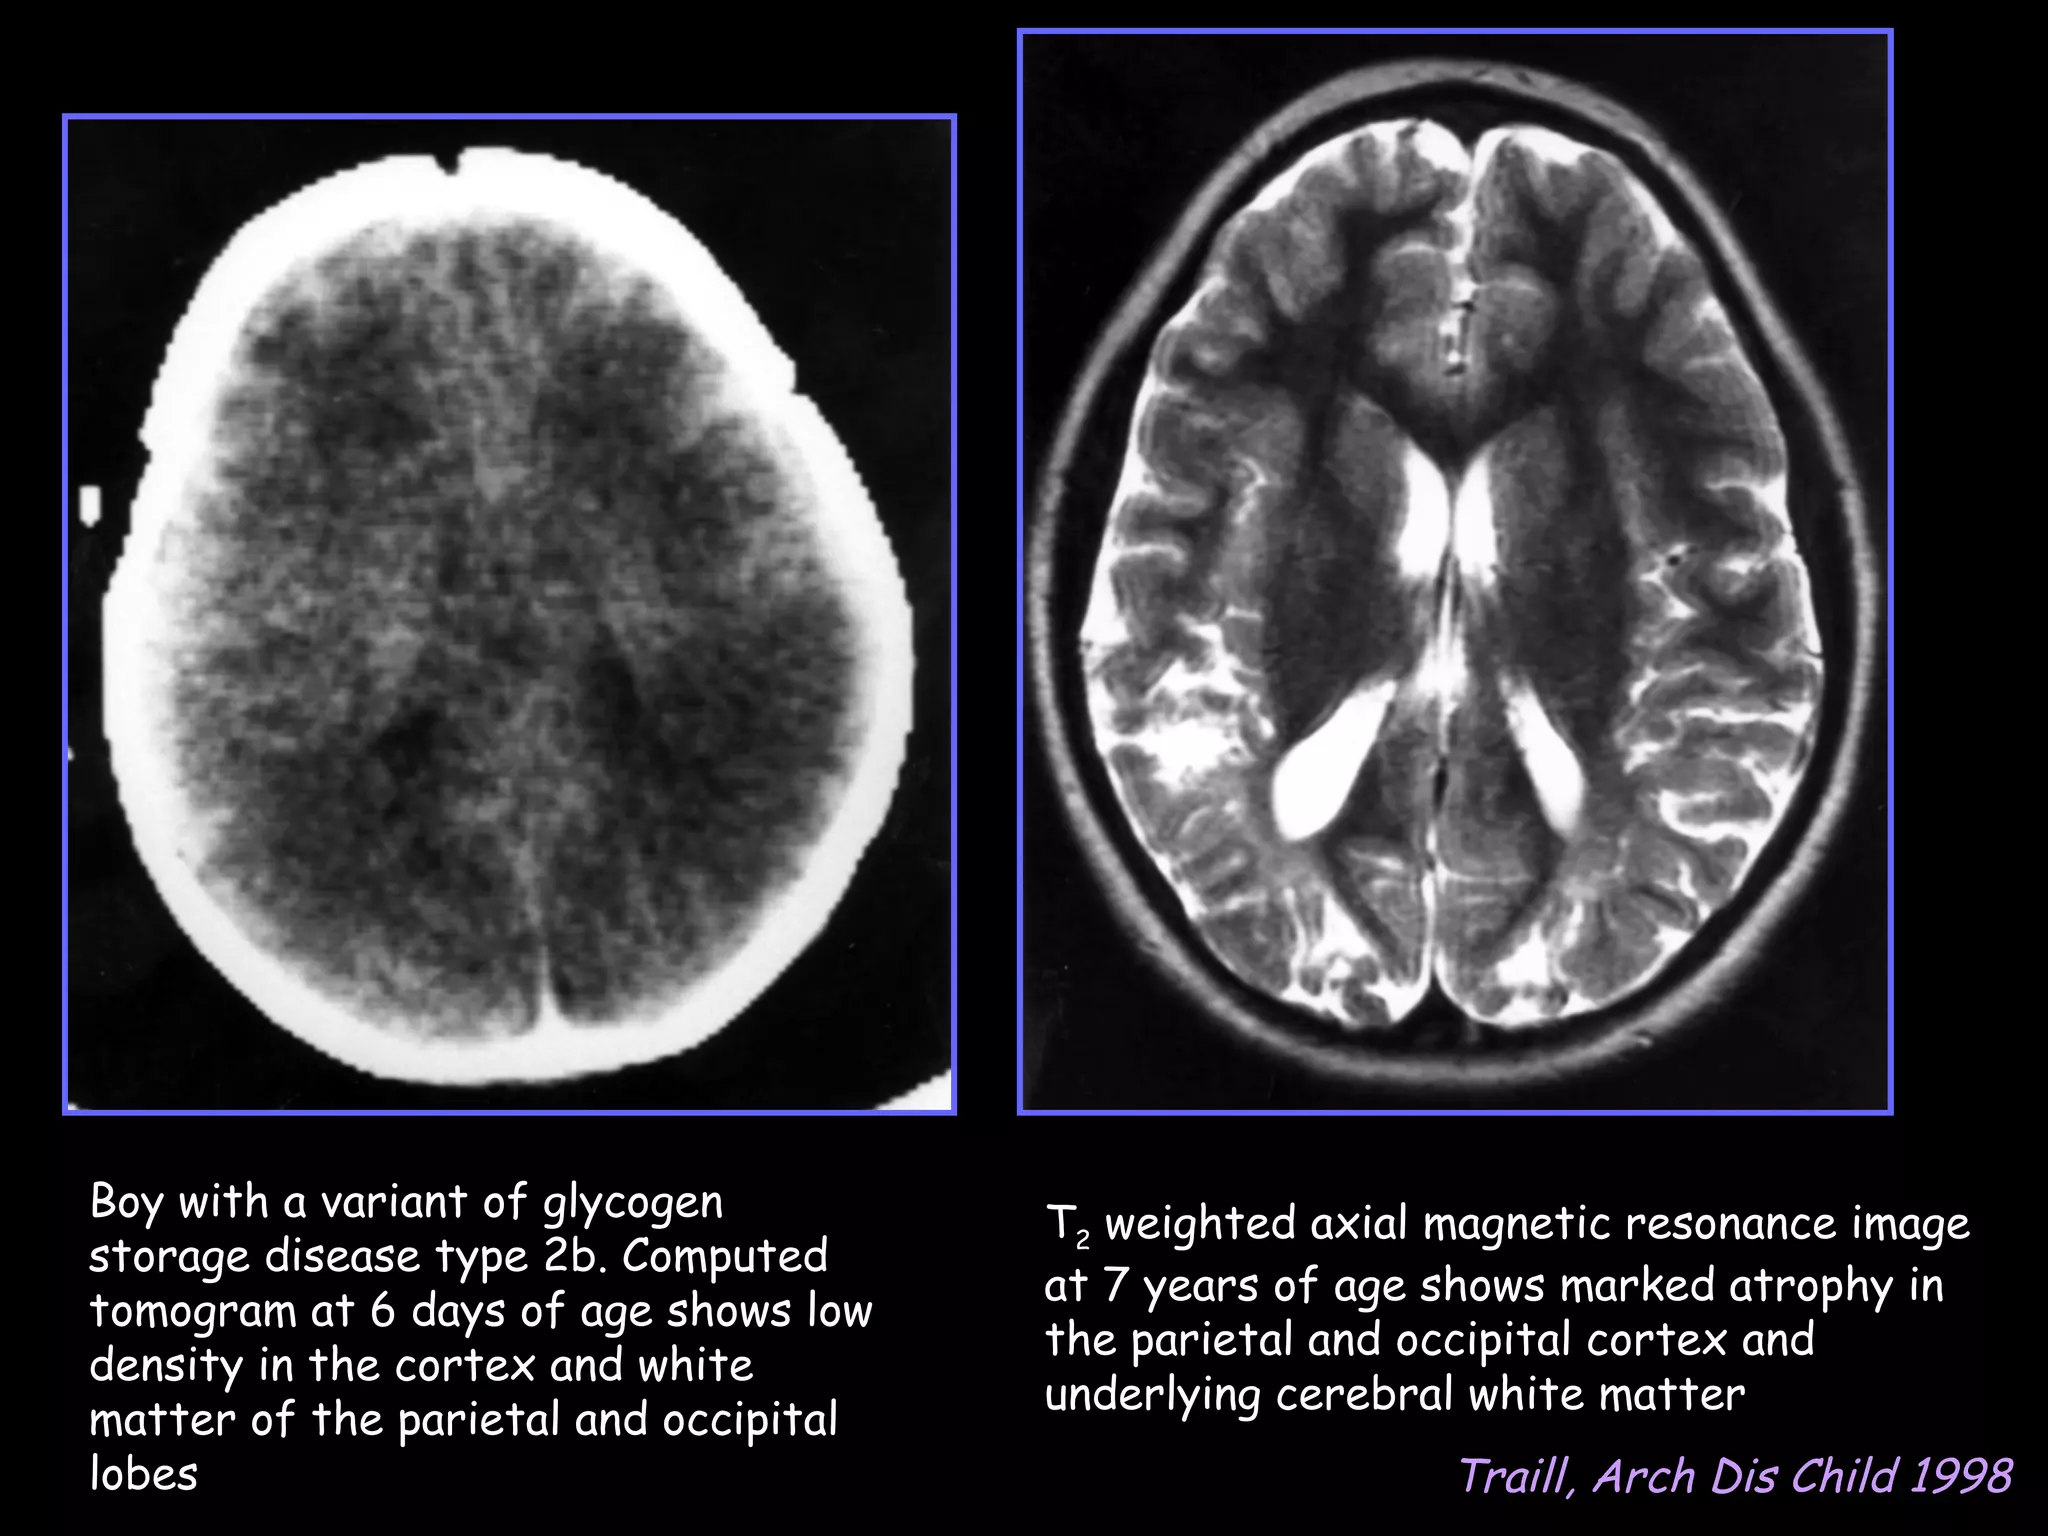

Boy with a variant of glycogen         T2 weighted axial magnetic resonance image

storage disease type 2b. Computed

at 7 years of age shows marked atrophy in

tomogram at 6 days of age shows low

the parietal and occipital cortex and

density in the cortex and white

underlying cerebral white matter

matter of the parietal and occipital

lobes                                                    Traill, Arch Dis Child 1998

Boy with avariant of glycogen T2 weighted axial magnetic resonance image storage disease type 2b. Computed at 7 years of age shows marked atrophy in tomogram at 6 days of age shows low the parietal and occipital cortex and density in the cortex and white underlying cerebral white matter matter of the parietal and occipital lobes Traill, Arch Dis Child 1998